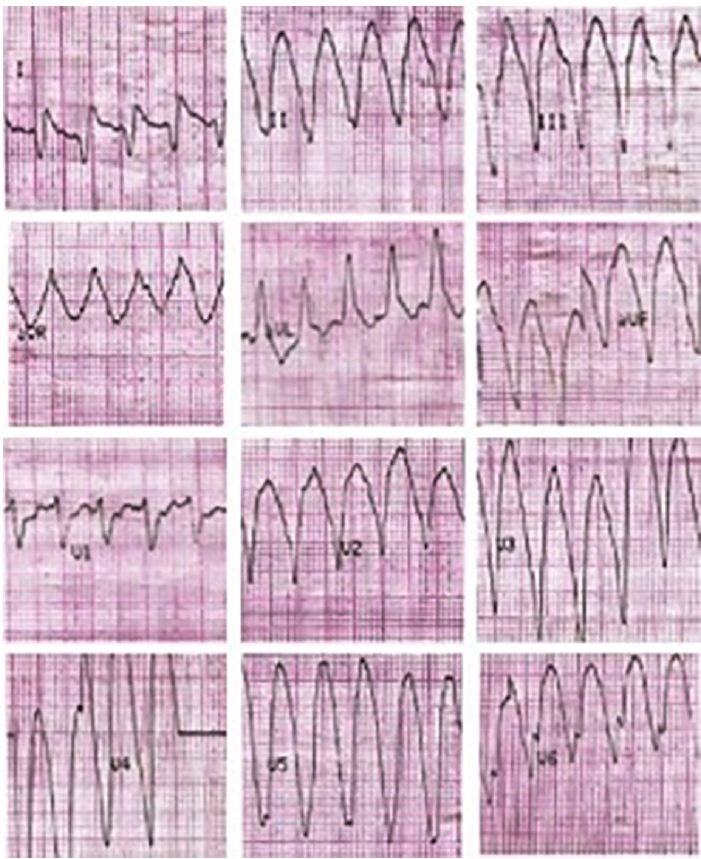

We present the case of a 30-year-old male patient with history of non-atherosclerotic dilated ischemicnecrotic cardiomyopathy, with reduced left ventricular ejection fraction (LVEF) (35%) and ventricular aneurysm (Figure 1), as a result of extrinsic iatrogenic lesion following anterior descending artery suture due to gunshot wound and urgent surgery. He subsequently underwent various hospitalizations for recurrent sustained monomorphic ventricular tachycardia (SMVT) (Figure 2a), leading to implantable cardioverter defibrillator (ICD) placement and substrate ablation, with favorable outcome.

Fig. 2a Monomorphic ventricular tachycardia with wide QRS complex, regular, at 190 bpm, with apical origin compatible with ventricular aneurysm.